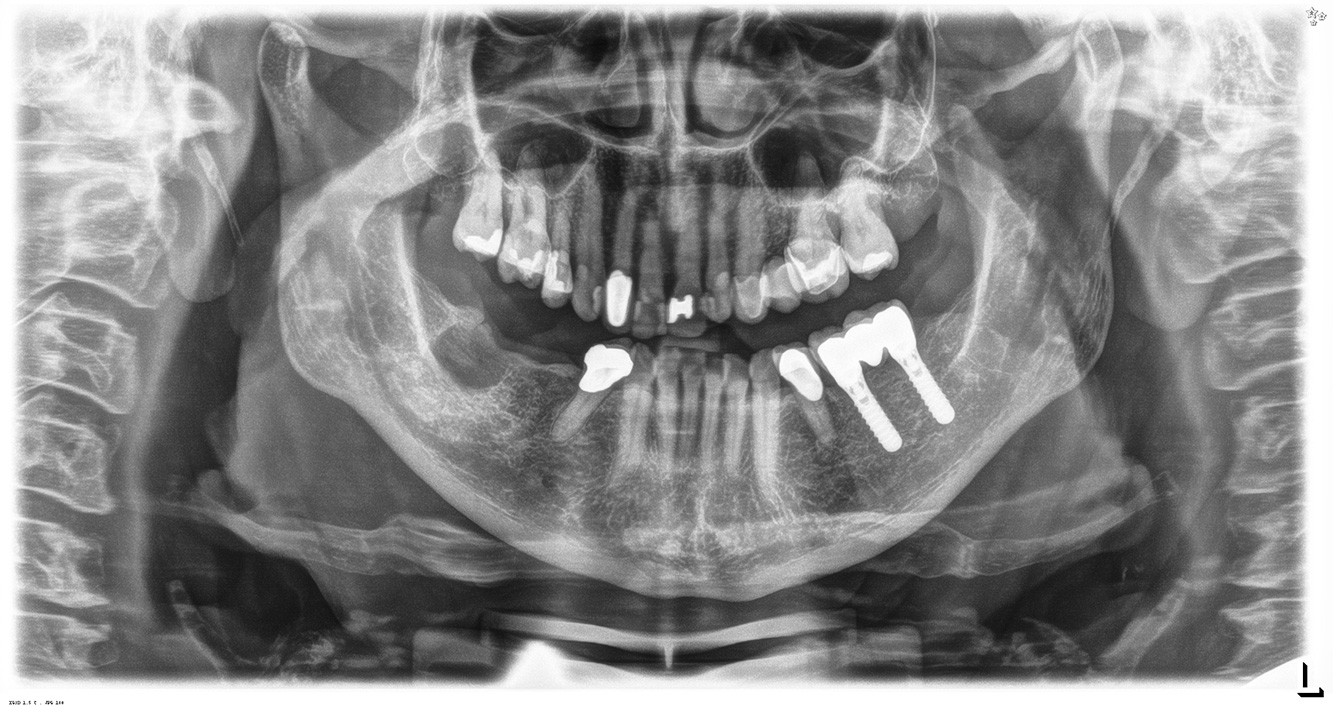

In the medical history, the 55-year-old patient states that he has no systemic disease and is not taking any medication. The patient’s lifestyle is similarly unremarkable. The patient has a few tooth restorations and two implants (2nd and 4th quadrants). On the basis of current findings, gingivitis is identified in an otherwise stable periodontal condition on the reduced periodontium (stage III, grade A). more

The healthy patient with pre-existing periodontal disease & peri-implantitis

A 52-year-old patient presents at a preventive care session. The patient has no systemic disease and is not taking any medication. He has had various dental treatments and also has two active carious lesions. In addition, the patient has four implants (2nd, 3rd and 4th quadrants). He is revealed to have early periodontal disease (stage IV, grade B). His periodontal condition is stable; a probing depth of Probing depths (ST) of 5 mm is only evident at the implant in region 36. Gingivitis is also identified. more